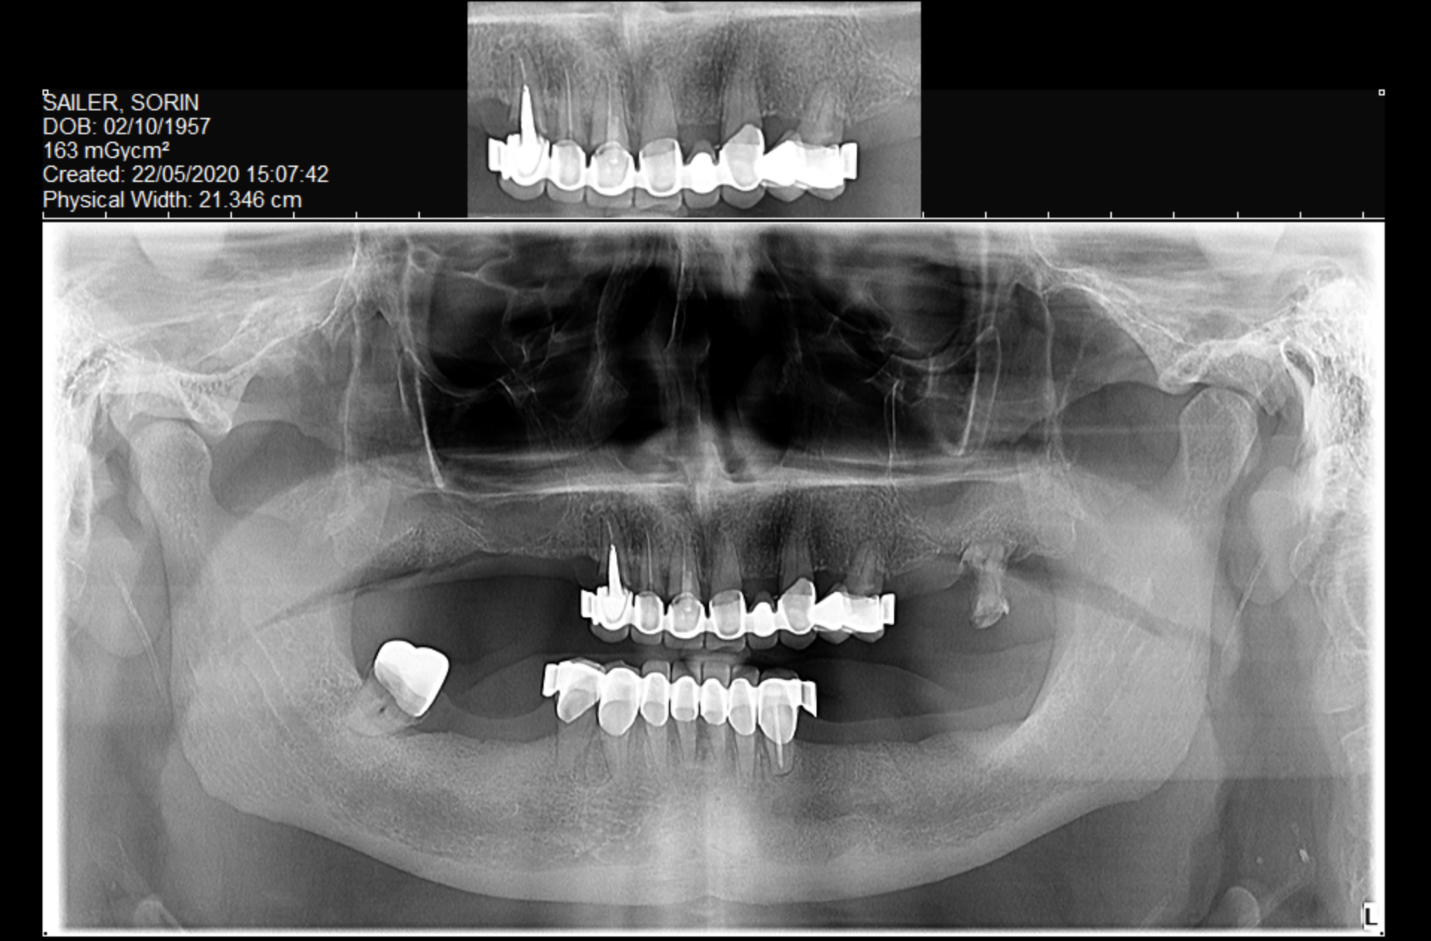

A patient presented with mobile dental bridges, significant difficulty chewing, and dissatisfaction with their overall dental esthetics. A preliminary assessment involved panoramic X-rays and intraoral scanning to evaluate dental status, bone quality, and available prosthetic space.

Cone Beam Computed Tomography (CBCT) scans were acquired for both the maxillary and mandibular arches. These scans provided critical insights into available bone volume, bone density, and anatomical considerations, forming a foundation for precise implant planning and guided surgery.

On the upper arch, for proper placement of implants, extractions with grafting were performed.

On the lower arch, a bone defect was present in the vicinity of the mental foramen and patient recalled having a multiple apicectomy performed in the past that, together with the lack of bone in the distal part of the left mandible, also needed the extraction protocols be implemented together with GBR procedures on the said defects.